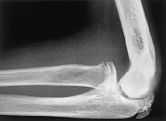

Se le realiza unaradiografía anteroposterior y lateral de codo derecho (cododominante) observándose, en esta última, a nivel delborde inferior del epicóndilo del húmero,afectación cortical con pequeñas erosionessubcondrales, sin observarse signos radiológicos sugerentesde fractura antigua a ningún nivel (fig. 1).

Figura 1. Radiografía lateral de codo derecho. Puede observarseuna pequeña erosión e interrupción de lacortical en el borde inferior del epicóndilo delhúmero.